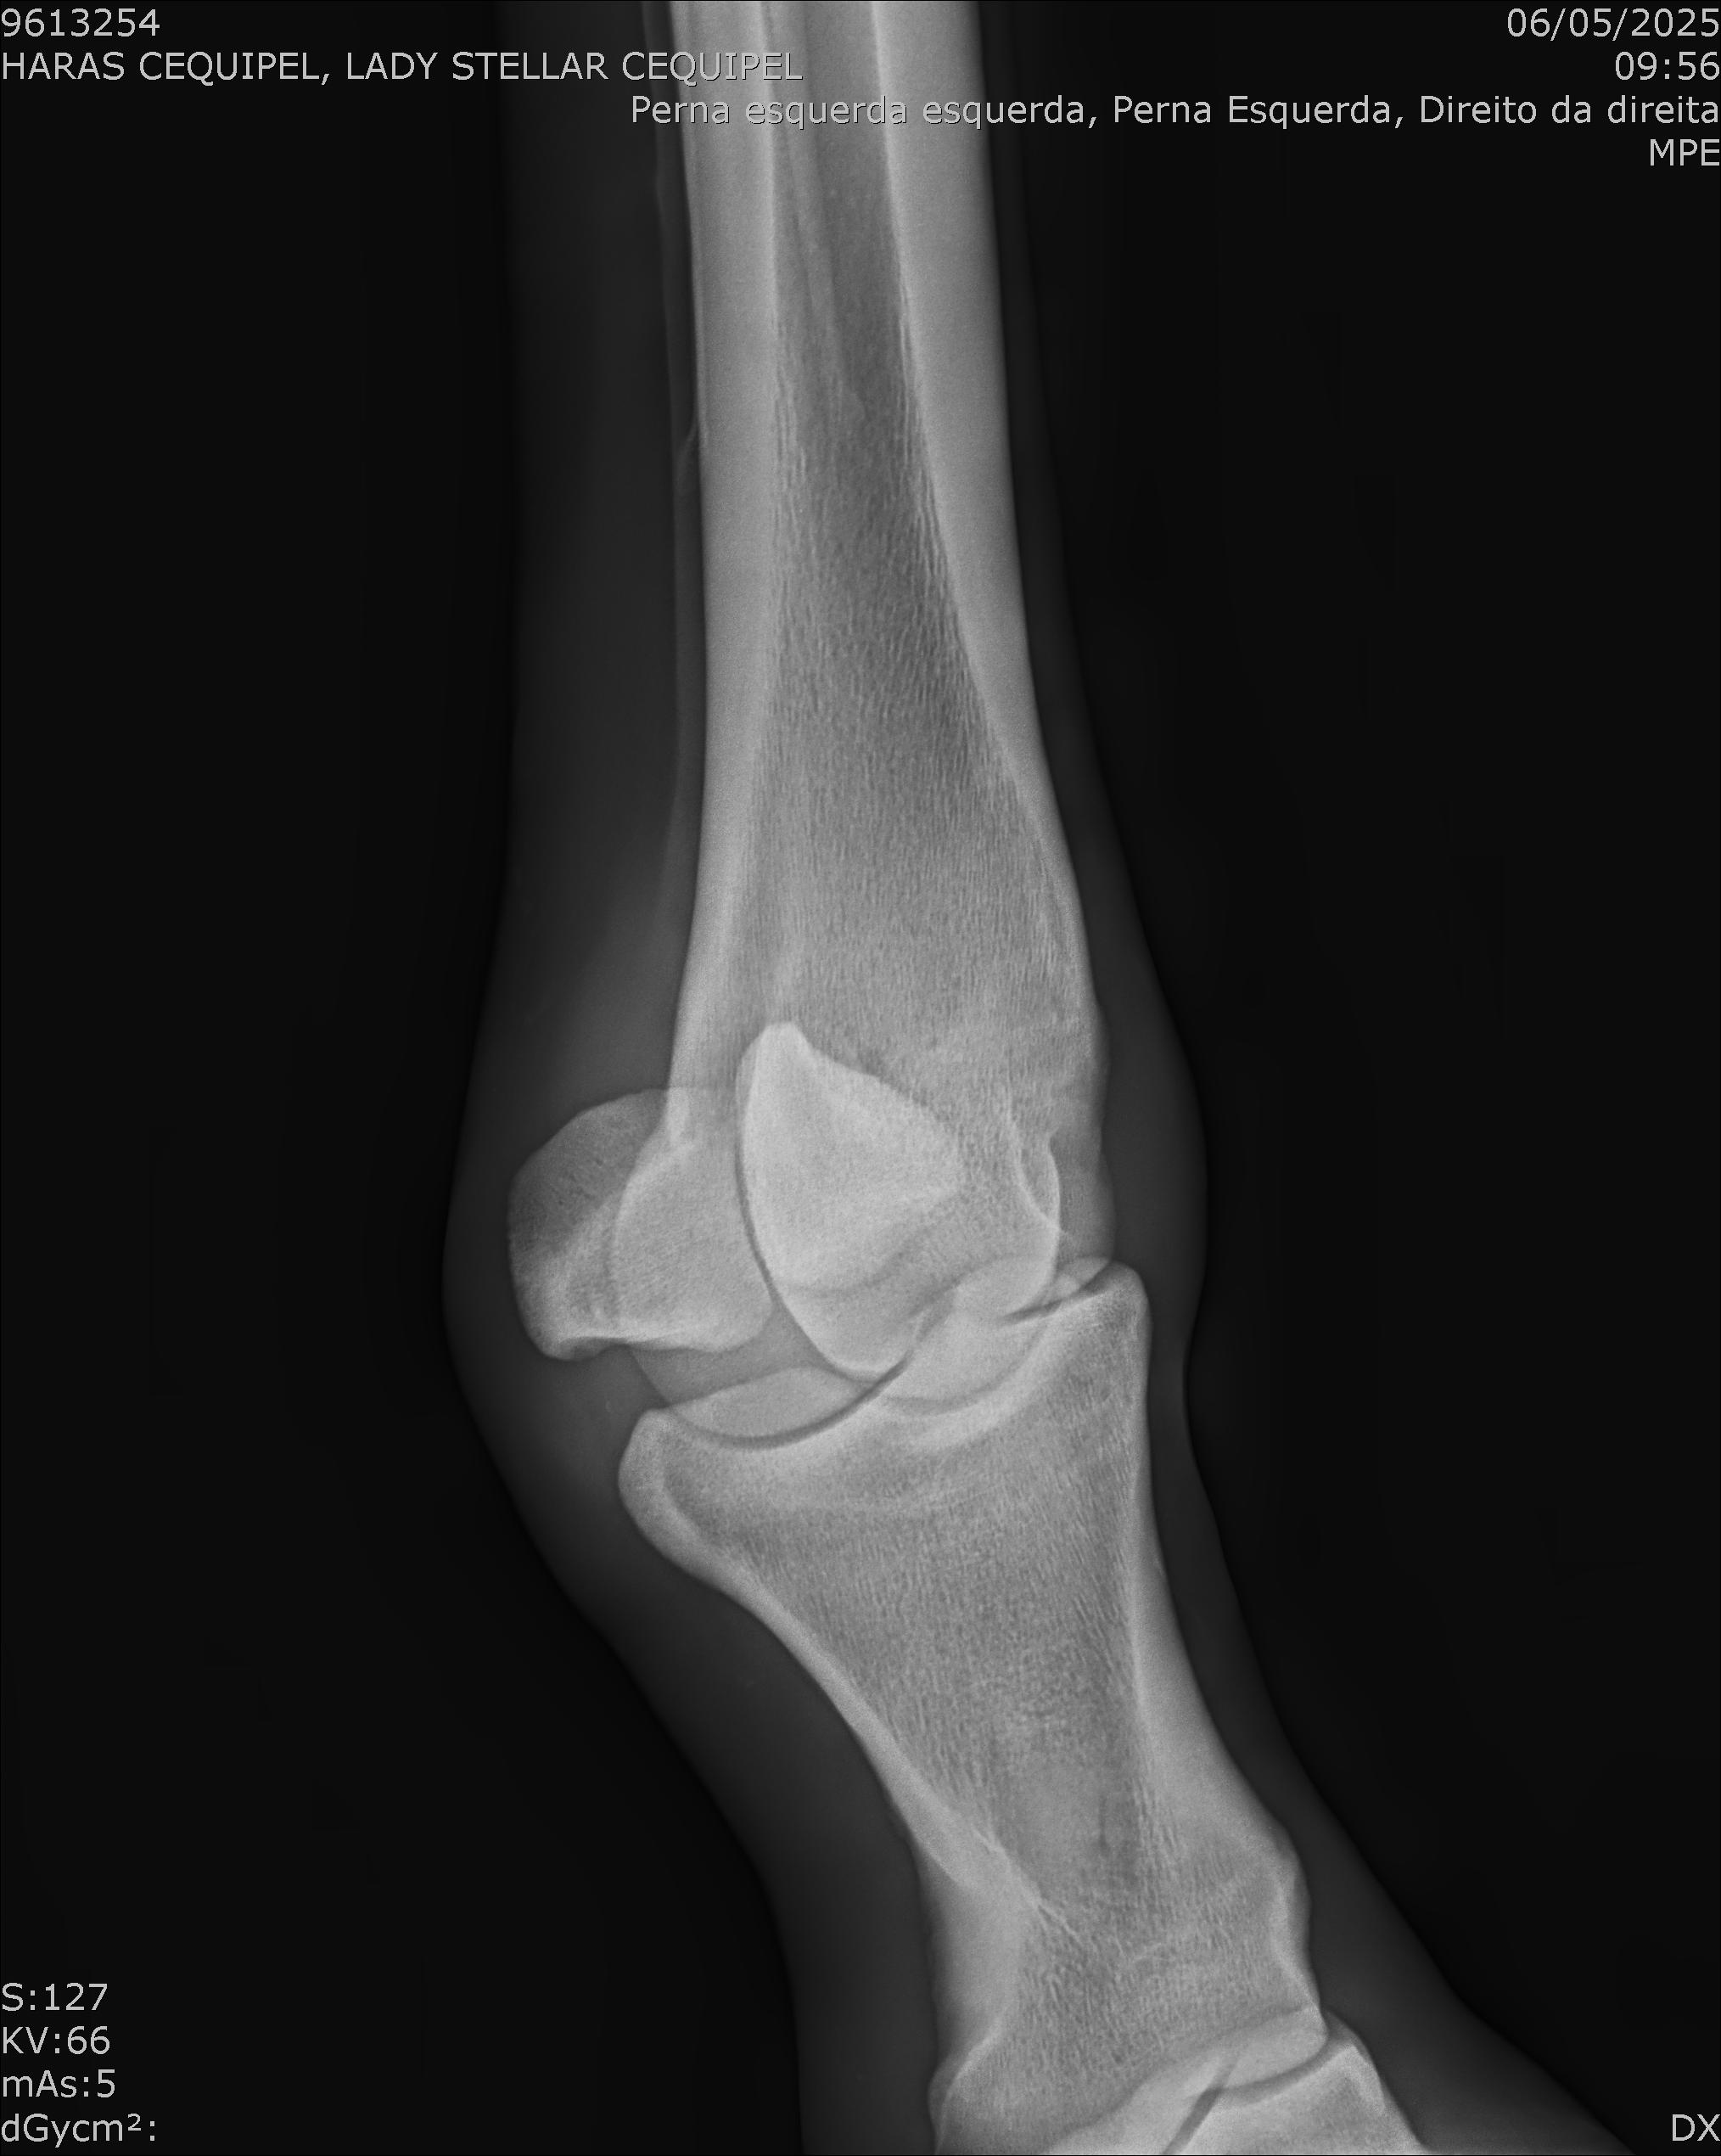

:: RAIOS-X DO LOTE